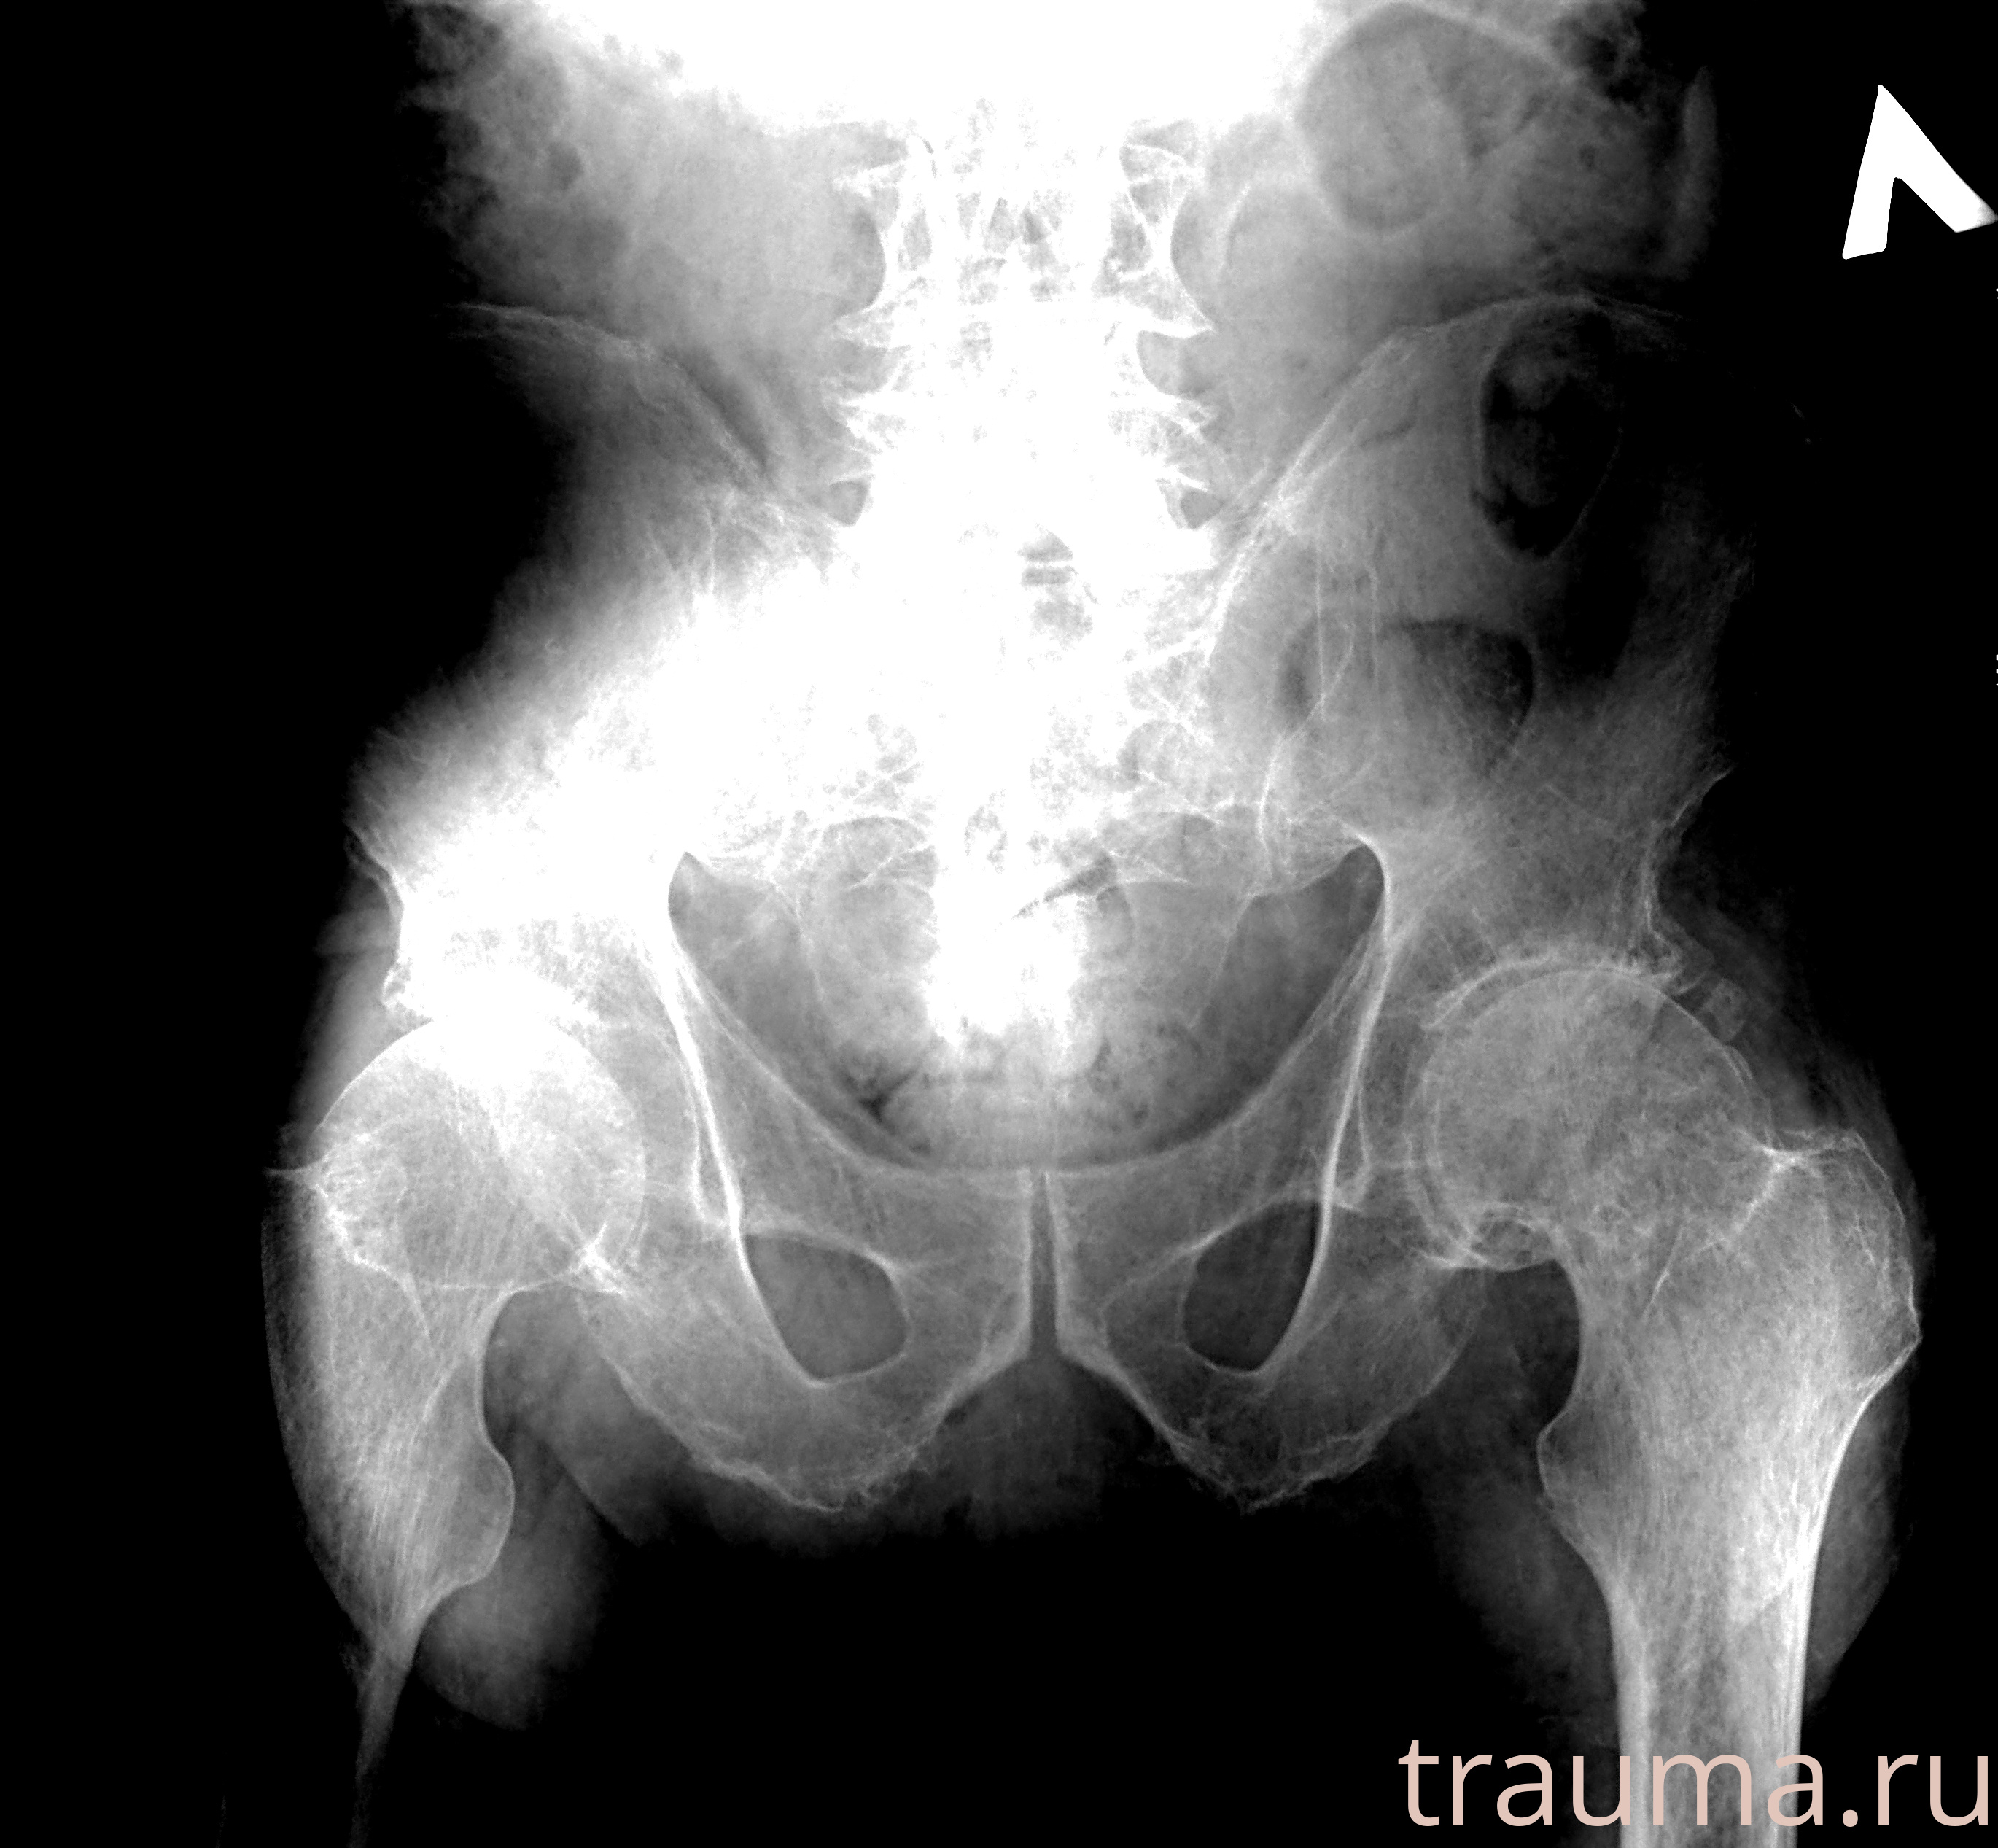

Первая помощь при переломе шейки бедра

Рентген на дому: по вашему адресу приезжает врач-рентгенолог, травматолог-ортопед с мобильным рентгеновским аппаратом, проводит диагностику травмы или заболевания, делает необходимые рентгенограммы, дает рекомендации по дальнейшему лечению. Получить качественные снимки в домашних условиях возможно благодаря уникальной методике, разработанной МосРентген Центром для института  Склифосовского